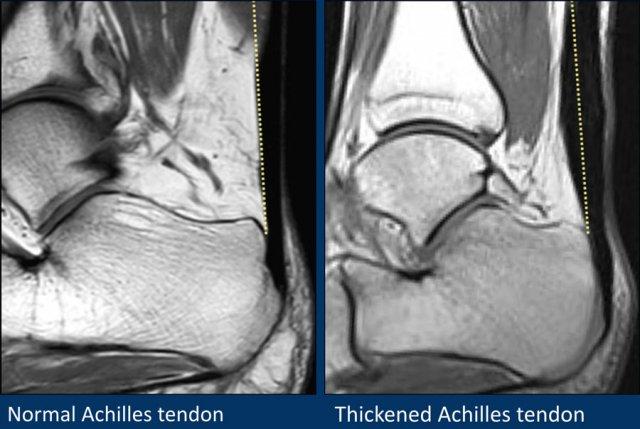

Gân Achilles

Gân Achilles là gân lớn nhất và khỏe nhất trong cơ thể người.

Hai tổn thương thường gặp nhất là bệnh lý gân và đứt gân.

Bệnh lý gân Achilles rất có thể do một loạt các vi rách gân làm suy yếu gân và gây sưng gân (hình bên phải).

Trên các hình ảnh mặt phẳng đứng dọc, gân Achilles phải có hình ảnh đường thẳng, không có dịch xung quanh và không có vùng dày khu trú.

Đường kính ngang 8 mm là ngưỡng giới hạn.